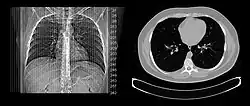

Lungs

A CT scan can be used for detecting both acute and chronic changes in the lung parenchyma, the tissue of the lungs.[41] It is particularly helpful because normal two-dimensional X-rays do not show such defects. A variety of techniques are used, depending on the suspected abnormality. For evaluation of chronic interstitial processes such as emphysema, and fibrosis,[42] thin sections with high spatial frequency reconstructions are used; often scans are performed both on inspiration and expiration. This special technique is called high resolution CT that produces a sampling of the lung, and not continuous images.[43]

Bronchial wall thickening can be seen on lung CTs and generally (but not always) implies inflammation of the bronchi.[44]

An incidentally found nodule in the absence of symptoms (sometimes referred to as an incidentaloma) may raise concerns that it might represent a tumor, either benign or malignant.[45] Perhaps persuaded by fear, patients and doctors sometimes agree to an intensive schedule of CT scans, sometimes up to every three months and beyond the recommended guidelines, in an attempt to do surveillance on the nodules.[46] However, established guidelines advise that patients without a prior history of cancer and whose solid nodules have not grown over a two-year period are unlikely to have any malignant cancer.[46] For this reason, and because no research provides supporting evidence that intensive surveillance gives better outcomes, and because of risks associated with having CT scans, patients should not receive CT screening in excess of those recommended by established guidelines.[46]